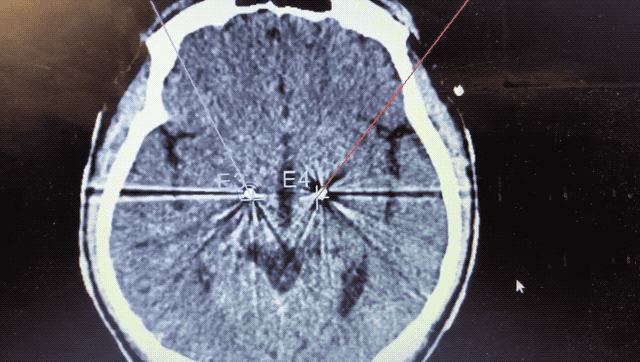

術中監測到典型核團信號

順利檢測到典型的核團信號后,再次植入刺激電極到相應位置,測試后即可完成單側的電極植入。對側只需借助機器人再次定位,并將檢測電極、刺激電極依次植入,最后,還需將刺激器植入患者胸前皮下。根據術后CT顯示,本手術雙側植入電極的位置與術前規劃路徑完全吻合,患者開機后,起搏器會開始沿刺激電極向患者核團實施高頻電刺激,以減輕疾病癥狀,提高患者的生活質量。

alt text

術后CT顯示雙側電極植入位置與規劃完全吻合